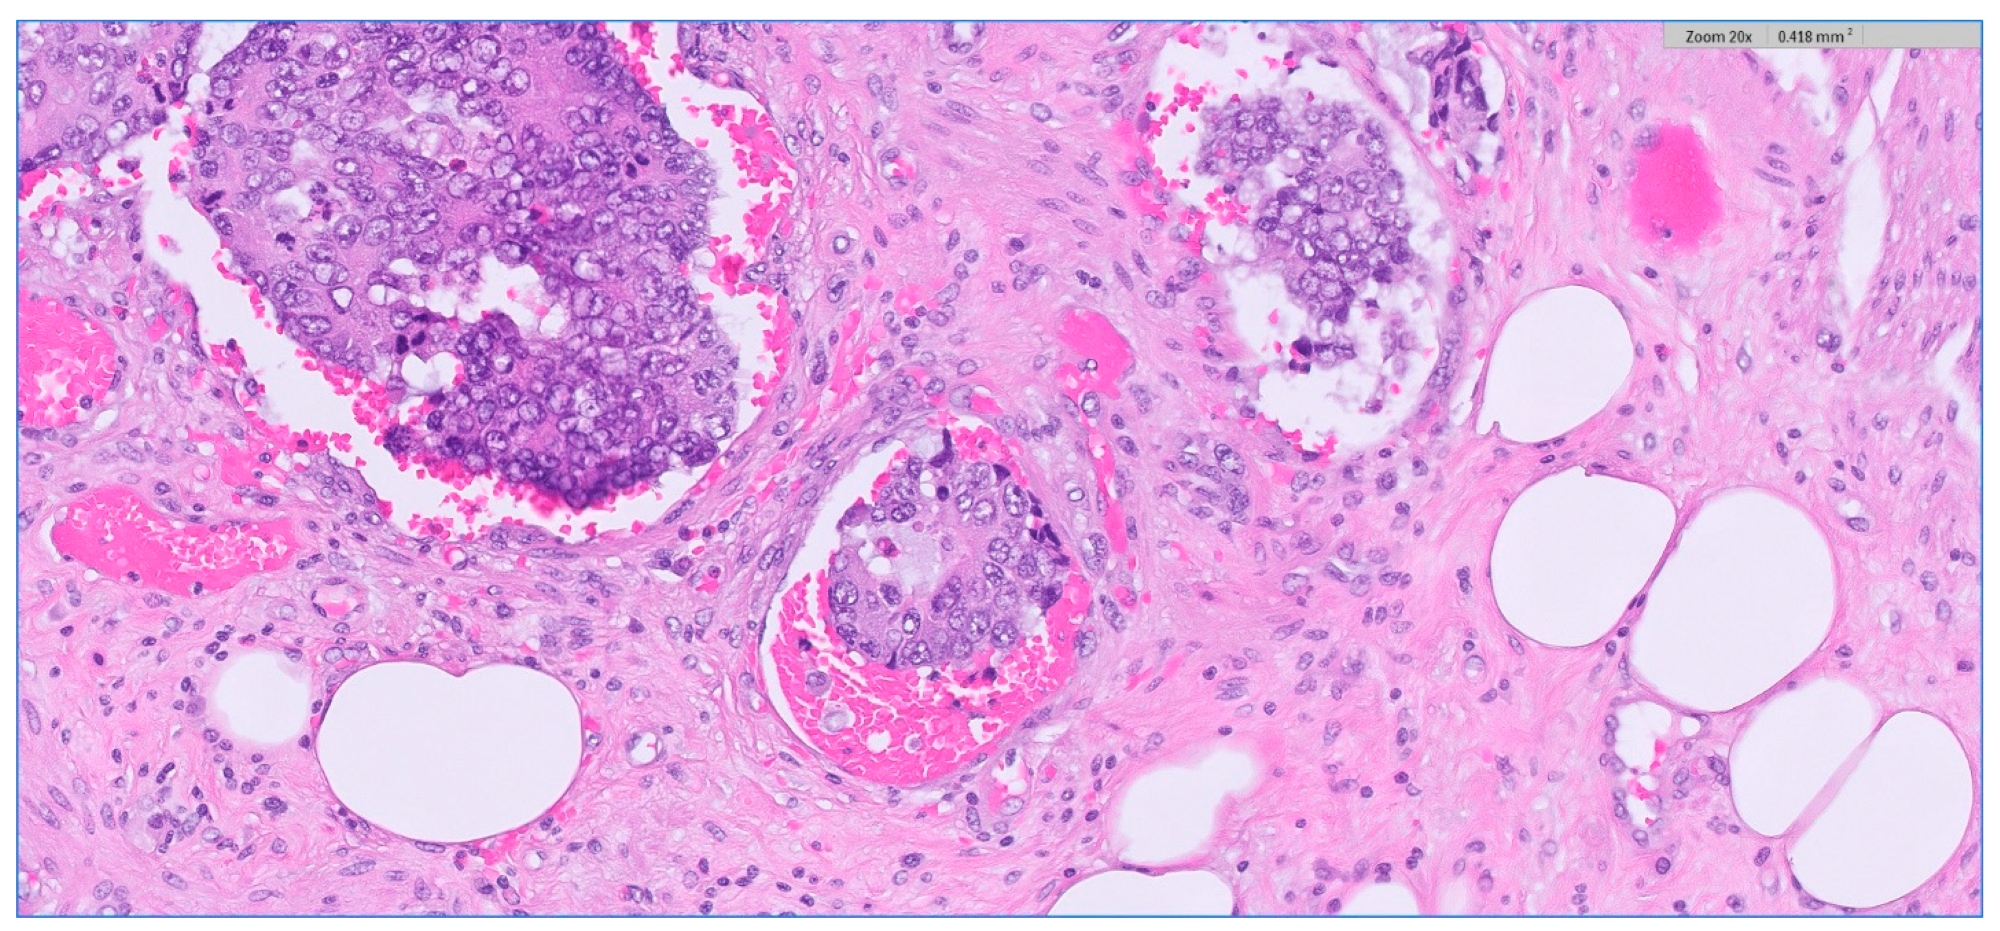

Figure 7.

Depiction of extramural lymphovascular invasion; carcinomatous emboli of rectal adenocarcinoma. HE stain × 20 magnification.